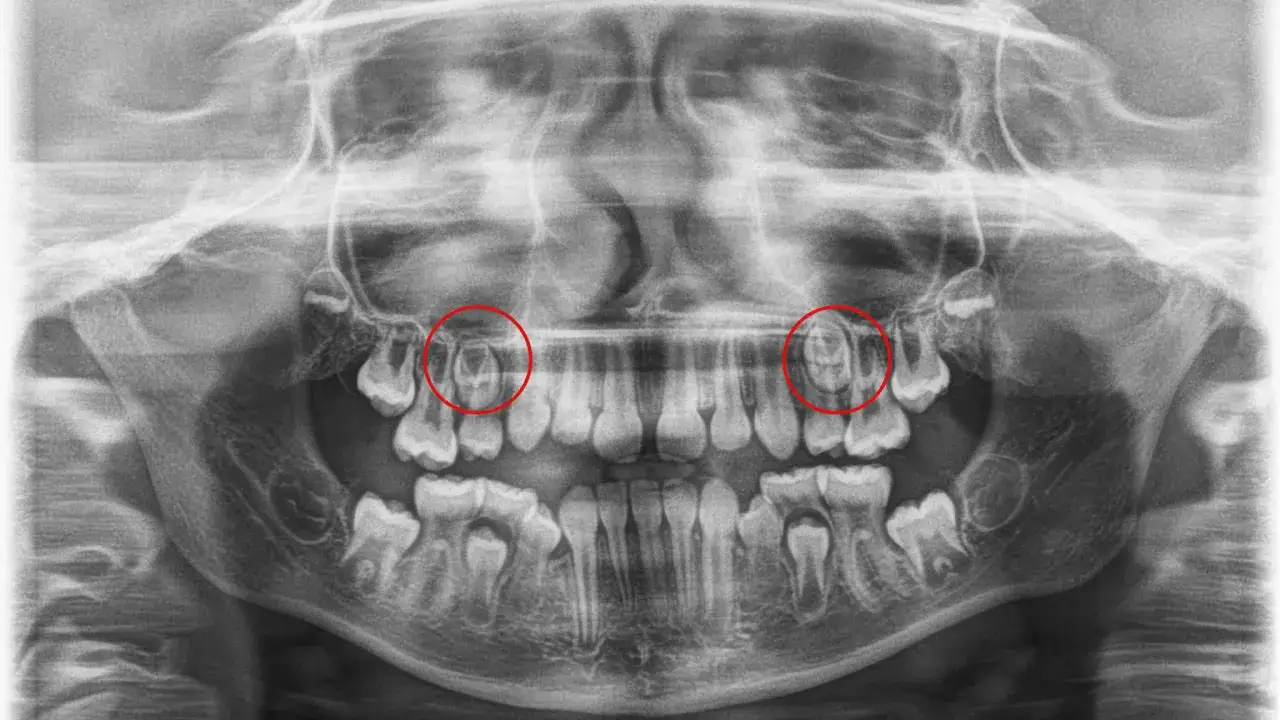

W przypadku braku zawiązków zębów stałych u dziecka, istotne jest przeprowadzenie odpowiednich badań diagnostycznych, które pozwolą na dokładną ocenę stanu uzębienia. Najczęściej stosowanym badaniem jest zdjęcie panoramiczne, które umożliwia zobaczenie wszystkich zębów w jamie ustnej oraz ich układu. Dzięki temu lekarz może ocenić, czy zęby stałe są obecne, ale nie wyrosły, czy też całkowicie brakuje ich zawiązków. To badanie jest szybkie i nieinwazyjne, co czyni je idealnym pierwszym krokiem w diagnostyce.

Kolejnym ważnym badaniem jest tomografia komputerowa (CBCT), która dostarcza szczegółowych obrazów trójwymiarowych. To badanie pozwala na dokładną ocenę struktury kości oraz lokalizacji zawiązków zębów. Dzięki tomografii lekarze mogą zidentyfikować potencjalne problemy, które nie byłyby widoczne na tradycyjnych zdjęciach rentgenowskich. Współpraca z dentystą oraz wykonanie tych badań jest kluczowe dla ustalenia dalszego postępowania w przypadku braku zawiązków zębów stałych u dziecka.